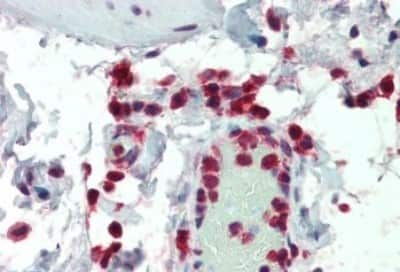

Immunohistochemistry-Paraffin: NCF1 Antibody [NB100-790]

Immunohistochemistry-Paraffin: NCF1 Antibody [NB100-790] - Staining of paraffin embedded Human Colon. Antibody at 5 ug/mL. Steamed antigen retrieval with citrate buffer pH 6, AP-staining.